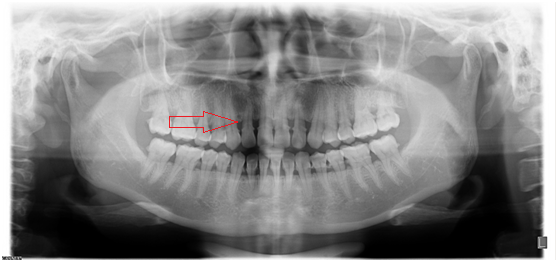

【根尖片】

◆磨牙龋齿

◆根管治疗完成后